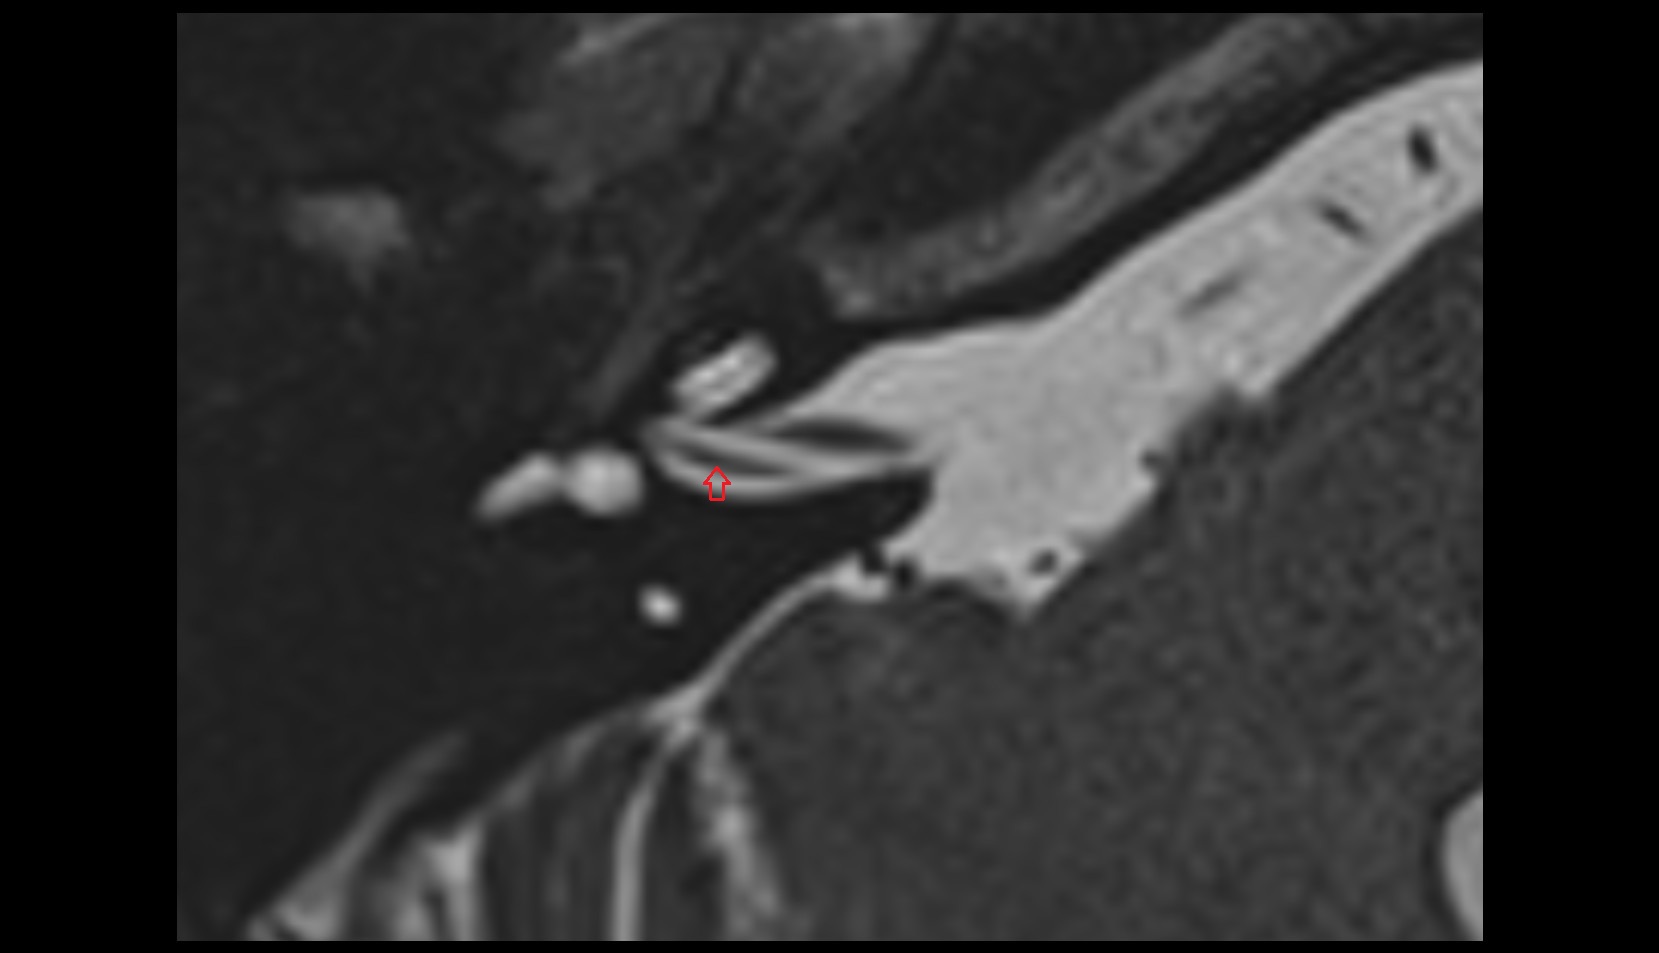

- Temporomandibular joint

- Articular disc of temporomandibular joint

- Attachment of inferior head of lateral pterygoid muscle

- Attachment of superior head of lateral pterygoid muscle

- Superior head of lateral pterygoid muscle

- Inferior head of lateral pterygoid muscle